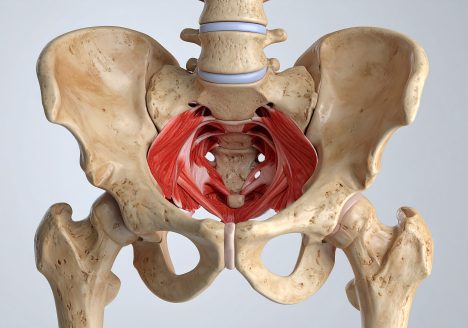

5 Signs You Need Pelvic Floor Physical Therapy

Danielle Ivie, DPT, CSCS | Founder of Powered by Movement Physical Therapy What is pelvic floor physical therapy? Great question! Pelvic floor physical therapy is exactly what it sounds like – rehab…

Get Rid of Your Low Back Pain with Pelvic Floor Muscle Training

Danielle Ivie, DPT, CSCS | Founder of Powered by Movement Physical Therapy Imagine this scenario: You work out regularly, usually feel pretty good, but every few months or so your back tightens…